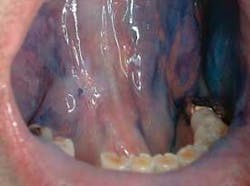

The clinical examples below show the appearance of lesions under incandescent light, chemiluminescence, and finally, the TBlue630™ stain.

Malignancies often begin with preneoplastic lesions, such as leukoplakia (white lesions). Twenty percent of leukoplakias display cellular dysplasia.This entity represents 85 percent of oral premalignant lesions. Erythroplakia (red lesions) and erythroleukoplakia (combination of white and red lesions), generally seen in elderly males, are severely dysplastic or have undergone malignant changes 91 percent of the time. These changes may be very difficult to see in their early stages depending on where they are located in the oral cavity.21-24

The light source is a disposable light stick contained within a retractor. The patient rinses with a flavored acetic acid solution, and then is examined. Normal epithelium absorbs the light and appears darker than abnormal epithelium, which reflects the light. As cells become dysplastic, the nuclear/cytoplasmic ratio increases. The enlarged nuclei reflect the chemiluminescent light, even from below the basement membrane. The lesion is marked on a mouth map provided in the kit, and photographed if possible. If inflammation or trauma cannot be ruled out, the patient returns in seven to 14 days. If the lesion persists, the toluidine blue (TBlue630™) dye is swabbed onto the site. Retention of the TBlue630™ indicates a need for referral for further study or biopsy. The TBlue630™ follow-up has a very high sensitivity and negative predictive value. There are very few false positives associated with this protocol. One study showed that TBlue630™ detected 16 out of 17 high-grade dysplasias.35 Other studies have indicated the extreme sensitivity of toluidine blue staining of premalignant lesions, including identification of lesions with negative biopsies that eventually converted to malignancies.36-38 The entire screening with the ViziLite® Plus kit takes less than three minutes and can be performed by a hygienist.